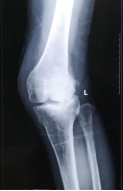

膝关节置换

3、保膝治疗 膝内翻(O型腿)、膝外翻(X型腿)的截骨保膝,恢复正常外形,改善早期关节炎。